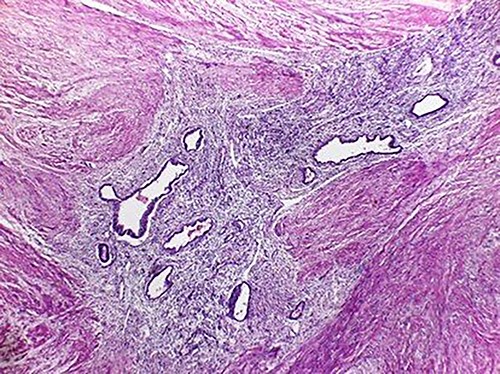

The microscopic study reported ileocolic intussusception and cecal endometriosis (Figs 4 and 5).

Low magnification image (4x); endometrial glands and stroma in the middle of the external muscular layer of the colon.